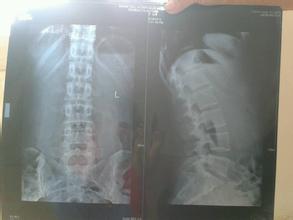

腰骨质增生如何治疗?腰骨质增生的治疗方法是比较多的,包括药物治疗、物理治疗、微创治疗以及手术治疗等等,治疗方法的选择与患者的实际病情有关。因此患者朋友不要盲目选择,要根据检查的结果让专业医生来制定适合自己的疗法,大家要重视。